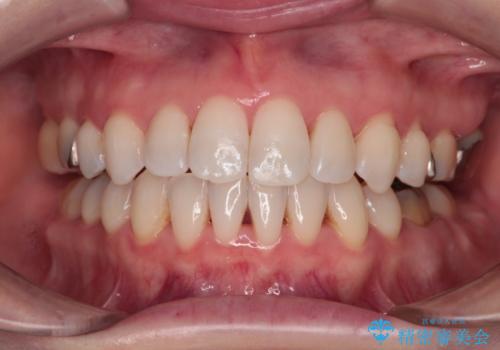

イレギュラーな大臼歯抜歯矯正であったため、治療期間の長期化が想定されましたが、何とか3年ちょうどで終えることができました。

今後は目立っている銀歯を中心にセラミッククラウンなどへ交換していく予定です。